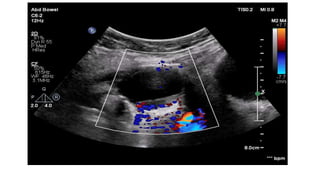

This document discusses the evaluation of right lower abdominal pain and lists appendicitis as a key cause. It notes that other potential causes include hemorrhagic cysts, heterotrophic pregnancy, salpingitis with pyosalpinx, funiculitis, and torsion of an undescended testis. The document was presented by Dr. A.S.M. Sufian of Cumilla Medical College Hospital and thanks the audience for their patience and listening.